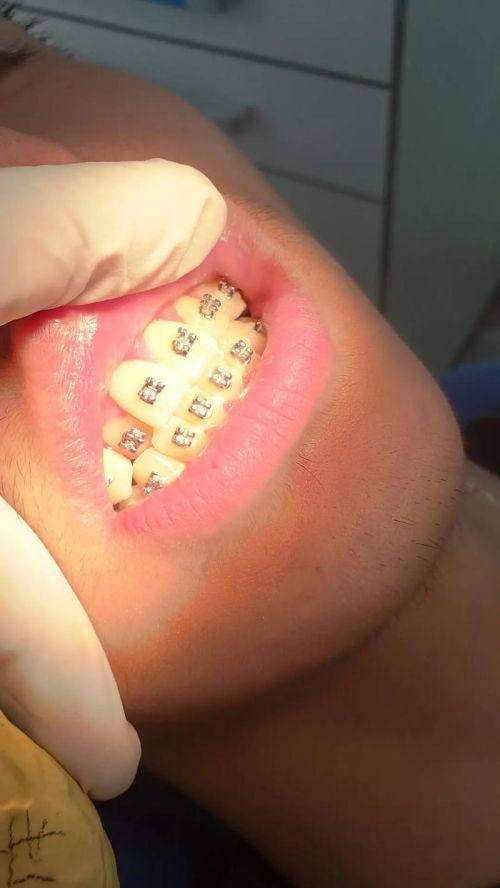

1. 矫正牙齿反合:牙齿反合不仅影响美观,还可能影响口腔功能。张亚科医生凭借丰富的经验和不错的技术,能够根据患者的具体情况制定个性化的矫正方案。他会综合考虑患者的牙齿排列、咬合关系等因素,采用合适的矫正方法,如传统金属牙套、隐形牙套等,帮助患者改善牙齿反合问题,修复正常的咬合和美观。

1. 患者李先生:我之前牙齿反合比较重度,不仅影响美观,而且吃东西也不太方便。听说张亚科医生在矫正牙齿反合方面特别有经验,就慕名而来。张医生给我做了详细的检查,制定了个性化的矫正方案。在矫正过程中,他非常耐心地解答我的疑问,每次复诊都认真调整牙套。经过一段时间的矫正,我的牙齿反合问题得到了明显改善,现在我的牙齿整齐了,笑容也更自信了。真的非常感谢张亚科医生,他的技术和服务都让我非常满意。